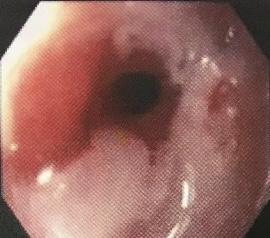

There is a spectrum of disorders ranging from the most common endoscopy-negative gastro-oesophageal reflux disease (GORD) to oesophageal mucosal damage, which can progress to ulceration and stricture formation, although only about 8% will have moderate or severe oesophagitis.

Esophageal stricture

డా. గన్నవరపు నరసింహమూర్తి, CC0, via Wikimedia Commons